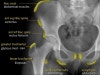

종류

복근(Abdominal muscles) : Iliac crest avulsion fx

봉공근(Sartorius) : Anterior superior iliac spine(ASIS) avulsion fx

대퇴직근(Rectus femoris) : Anterior inferior iliac spine(AIIS) avulsion fx

중둔근 및 소둔근(Gluteus medius & minimus) : Greater trochanter(GT) avulsion fx

장골근(Iliopsoas) : Lesser trochanter(LT) avulsion fx

내전근(Adductors) : Symphysis avulsion fx

햄스트링(Hamstring) : Ischial tuberosity avulsion fx